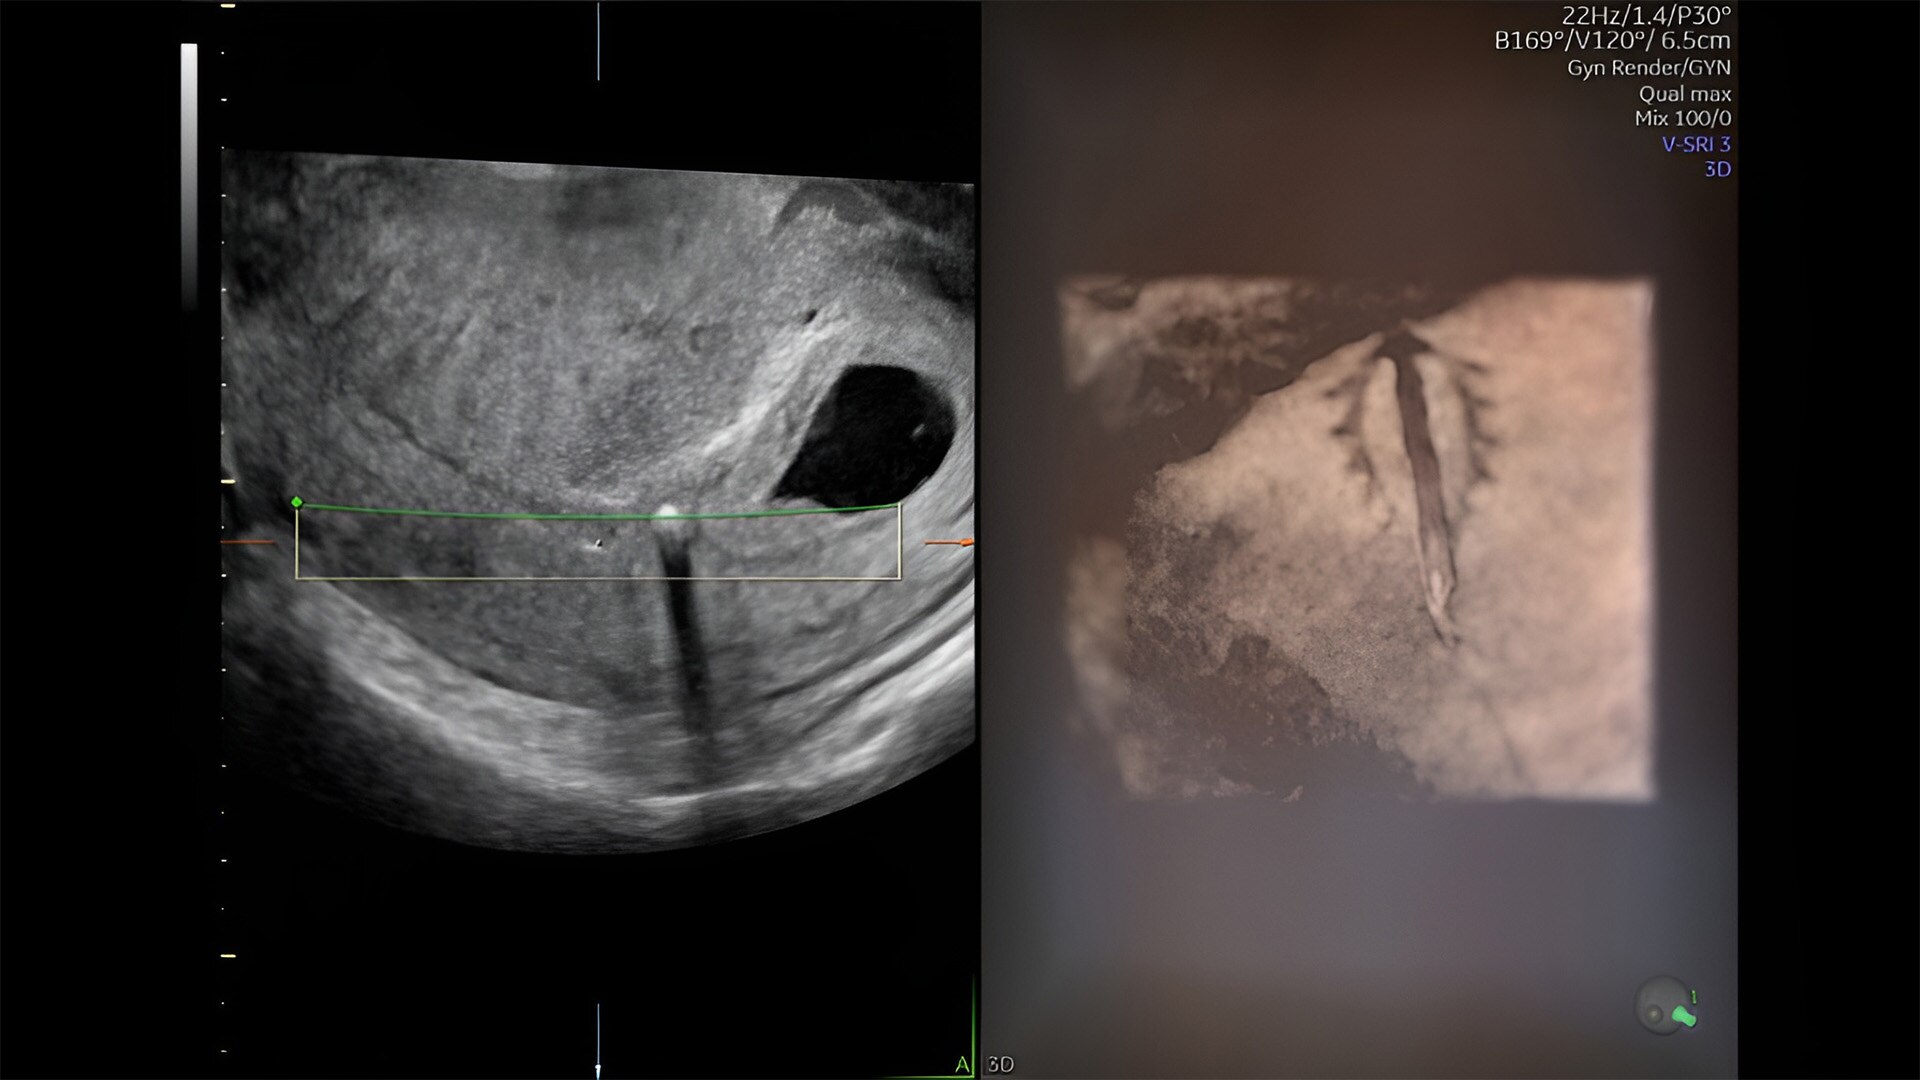

Fetal heart evaluation

Get to the heart of the matter

Identifying fetal cardiac abnormalities earlier means you can intervene sooner, plan for delivery, and potentially improve outcomes. The Voluson Expert 22 provides a full solution of progressive tools, to help distinguish the tiniest structures with stunning clarity to provide patient answers faster.